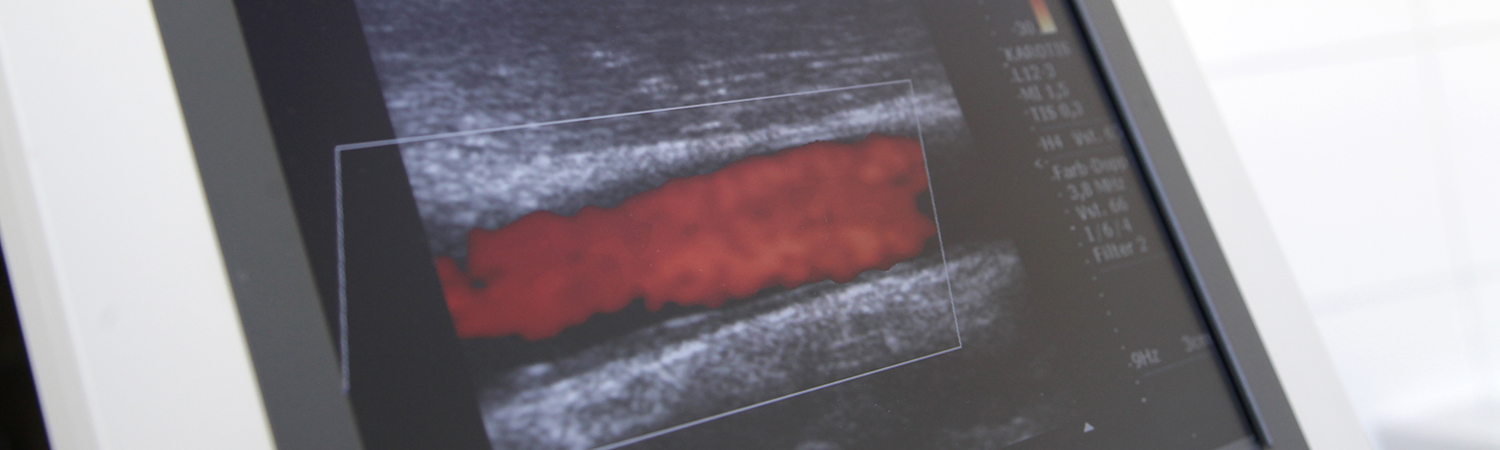

EKG, Belastungs-EKG, Langzeit EKG, Langzeitblutdruckmessung,

Lungenfunktion, Bauchultraschall, Schilddrüsenultraschall,

Herzultraschall( Echo), Ultraschall der Halsgefäße (Carotisduplex)